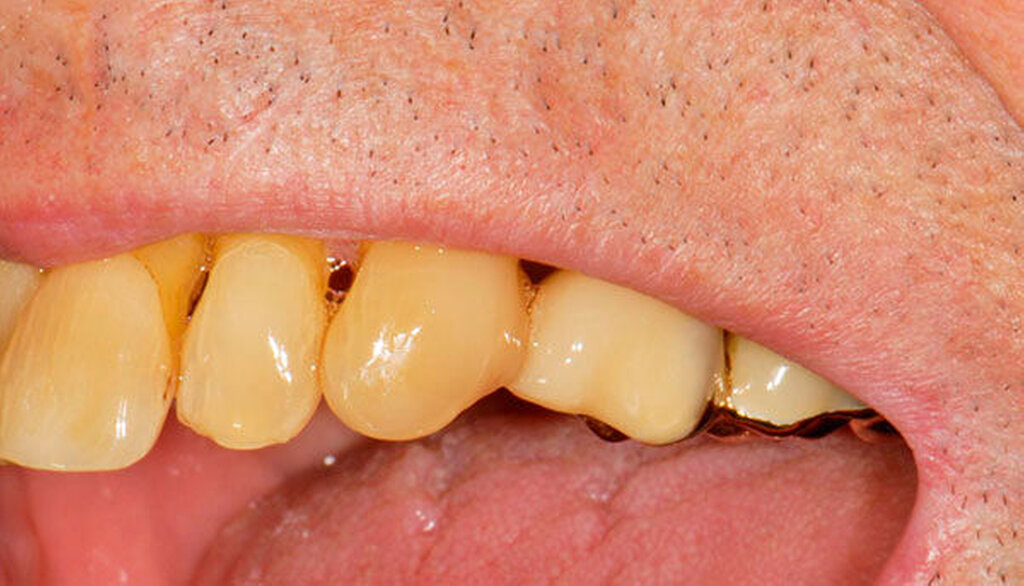

Abbildung 4: Anliegen eines 76,5-jährigen Patienten (Anfrage per E-Mail). Zitat: „Mich plagt eine … Entzündung des Mundraums, die auch das Zahnfleisch meiner Zahnstummel angreift, weshalb ich nur noch Breiartiges zu essen vermag. Ein Angsthase wie ich geht zum Zahnarzt NUR unter dem Eindruck akuter Schmerzen!“

Damit wird die Hygienefähigkeit zumindest partiell verbessert und Spielraum für künftige Planungen und Vorgehensweisen unter besseren Bedingungen belassen. Das Procedere ist in den Abbildungen 4 und 5 beschrieben. Bei dem in Abbildung 4 vorgestellten Patienten lag eine Oralphobie im Seniorenalter vor. Die Verlaufsbeschreibung macht deutlich, dass selbst im fortgeschrittenen Alter eine Adaptation an zahnärztliche Interventionen im Einzelfall noch möglich ist.

Üblicherweise werden frakturierte Zahnkronen beziehungsweise Wurzelreste restaurativ wieder aufgebaut oder es erfolgt eine Extraktion. Im Seniorenalter erscheint es hingegen manchmal als Kompromissmaßnahme vertretbar, Wurzelreste vorerst zu belassen und etwa mit adhäsiv eingebrachtem Komposit knapp über Gingivahöhe abzudecken. Dies bietet sich vor allem dann an, wenn die Wurzelkanäle bereits obliteriert und endodontische Interventionen nicht erforderlich sind (Tabelle 4) [Staehle et al., 2017].